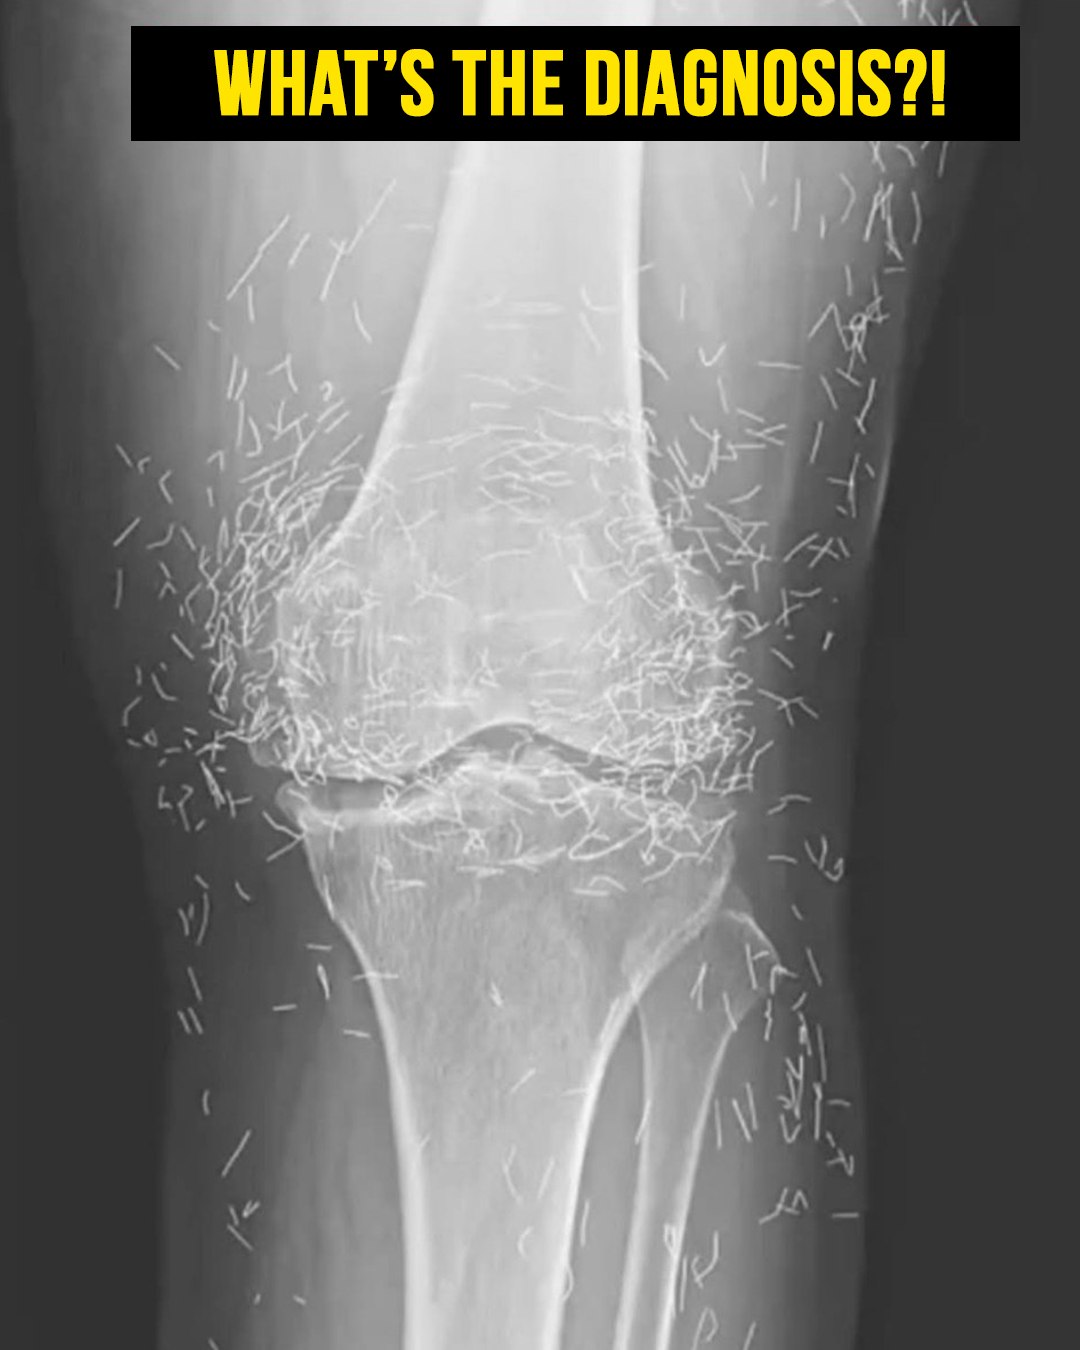

Acupuncture, an alternative treatment that has been around for centuries, involves the insertion of needles into specific points on the body to alleviate pain or address various health issues. In this particular case, the needles—likely made of gold—were deliberately left in her knees to provide ongoing stimulation.

He also cautioned that needles left embedded can interfere with X-ray interpretations. “The needles may obscure some of the anatomy,” Guermazi mentioned in 2013.

Even more alarming, leaving needles in the body can pose risks for future medical imaging. “The patient cannot undergo an MRI because the needles left inside may shift and harm an artery,” Guermazi noted.